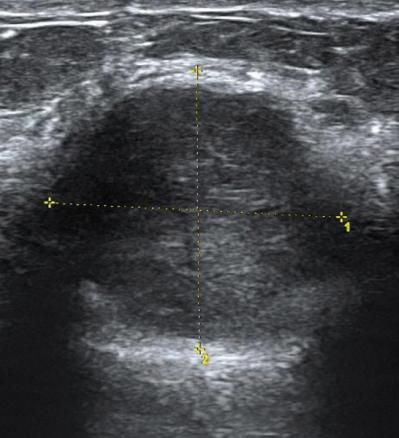

Tumeurs du sein - Cancer nodulaire chez une femme de 30 ans

Echographie, masse BIRADS 5.